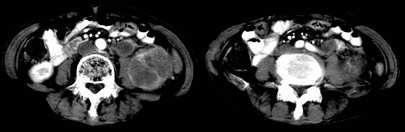

左肾不规则软组织肿块,内见低密度坏死区,与正常肾实质分界不清,左肾明显增大,增强呈不规则条索状强化,肾盂及左输尿管上段扩张。肾周脂肪层受侵、模糊。印象:典型左肾癌。

左侧肾癌并肾静脉癌栓.腹膜后淋巴结肿大转移.

顺便说几句。肾癌的转移,肾静脉的转移尤为常见,他可以顺沿静脉直至下腔静脉,这种转移,临床中也不少见,笔者遇到过数例。这种转移对于临床来说有较大意义,直接影响手术的成功、手术的方式等,临床有不少肾癌切除术后,静脉残端复发病例。不知楼主有意还是无意,没有给静脉期,或者左肾静脉充盈的图象。

左肾癌累及左输尿管,左肾静脉无受累征象。